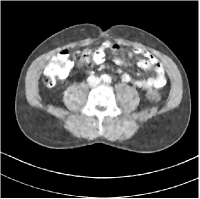

We conduct experiments on three slices (L067-slice100, L192-slice100, L506-slice100) of the Mayo Clinic data. Fig. 2 shows the reconstruction of L067-slice100 using FBP, PWLS-EP, PWLS-ST, PWLS-MRST2, PWLS-MRST3, PWLS-MRST5, and PWLS-MRST7, respectively at incident photon intensity . TABLE I lists the RMSE, PSNR, and SSIM values of reconstructions of the three test slices, with the best values bolded. The two-layer model (MRST2) provides the best RMSE and PSNR values among the methods. However, when we consider the SSIM criterion, MRST5 and MRST7 outperform ST and MRST2. So which MRST model is better? By observing the reconstructed images, we see that although MRST2 and ST have lower RMSE and higher PSNR values than MRST5 and MRST7, they sacrifice some sharpness of the central region and suffer from loss of details. The deeper models have a more positive effect in maintaining subtle features, which is clearly more essential to clinic medical diagnosis. Furthermore, after considerable parameter tuning, we have observed that the deeper models offer more stable image quality as is varied, i.e., they are more robust to oversmoothing.